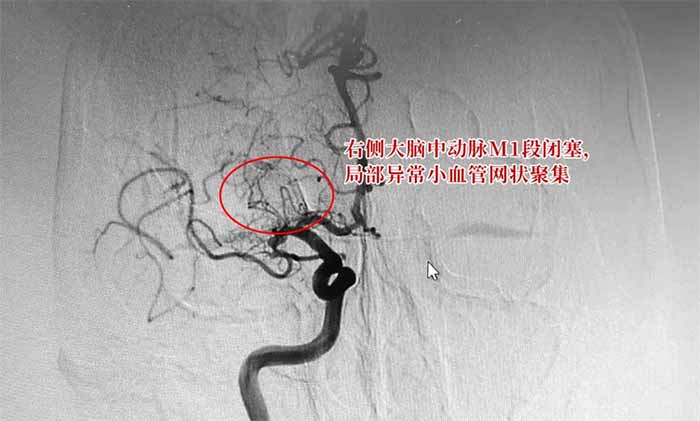

煙霧病是一種慢性閉塞性腦血管疾病,以雙側(cè)頸內(nèi)動(dòng)脈末端和(或)大腦前動(dòng)脈、大腦中動(dòng)脈起始部緩慢進(jìn)展性狹窄以致閉塞,出現(xiàn)代償性異常血管網(wǎng)為特點(diǎn),因其異常血管網(wǎng)在腦血管造影時(shí)似“煙霧繚繞”,故稱為“煙霧病”。

▲ 煙霧病DSA檢查影像